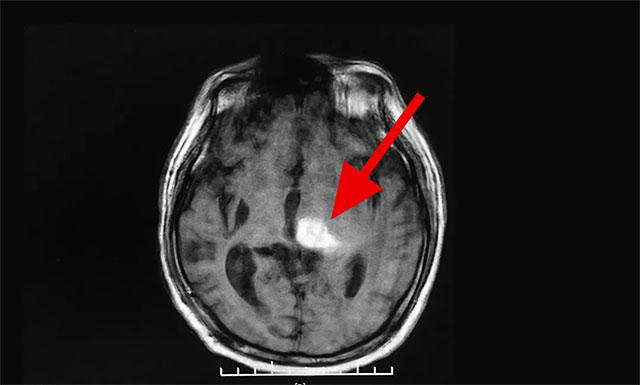

“這是我老伴第二次腦出血了,當時就診的醫(yī)生就告訴我說,這次他腦出血很嚴重,雖然他腦出血量不是很大,但出血點比較多,部位也很關(guān)鍵。”劉女士回憶道,根據(jù)病歷上反映:患者張先生是左側(cè)基底節(jié)區(qū)腦出血,并破入腦室,同時雙側(cè)基底節(jié)及半卵圓區(qū)多發(fā)腔隙性腦梗死。“醫(yī)生讓我們家屬做好心理準備,即使保住了性命,可能也要長期偏癱在床了”,劉女士如是說。

▲ 患者腦出血比較嚴重,仍然處于昏迷狀態(tài)

入院后,完善患者各項檢查,戴秀珍主任對其進行了認真而全面的身體檢查,發(fā)現(xiàn)患者右側(cè)瞳孔對光反射遲鈍; 不能言語,定向力、計算力、記憶力基本喪失; 右側(cè)肢體肌力為0級,左側(cè)肢體肌力為3級,四肢肌張力都比較高。